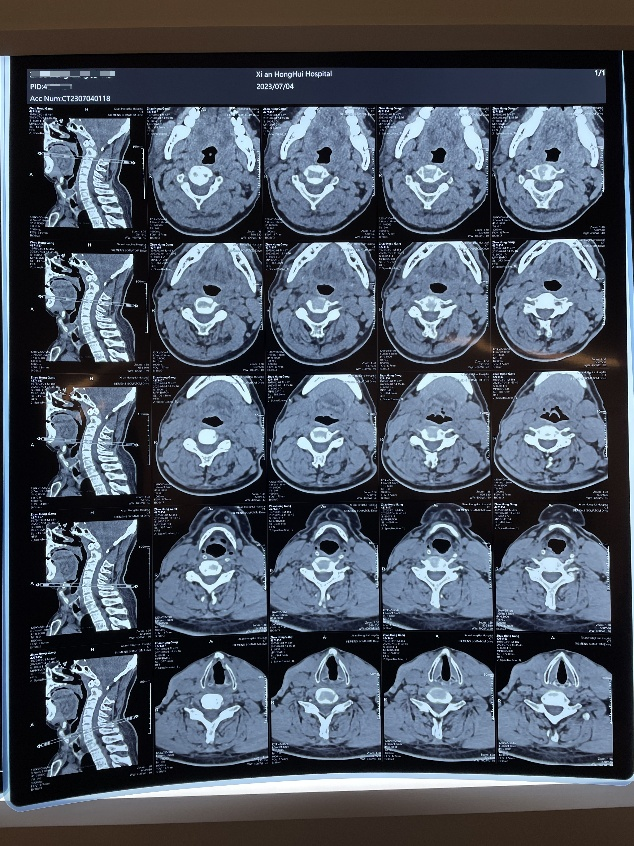

6.核磁图像、CT图像翻拍

以翻拍磁共振图像为例,翻拍时因为磁共振影像图很大,一张上多个图像,所以只拍一张照片,难以拍清楚细节,医生无法通过照片获取有效信息。

因此先拍一张整图,将一张磁共振图进行分区,并按分区顺序局部放大拍摄,尽可能的将片子上的细节拍摄清楚。CT图像翻拍操作一致。

正确示范

(整图拍摄)